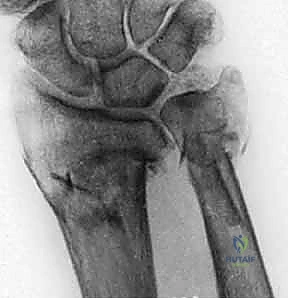

1. الأشعة السينية (X-rays): بوضعيات متعددة (أمامية خلفية، وجانبية دقيقة). الوضعية الجانبية الحقيقية (True Lateral) حاسمة لاكتشاف أي خلع جزئي في المفصل (DRUJ).